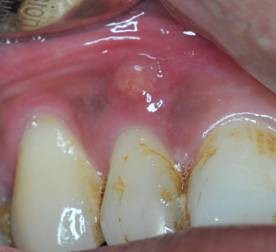

Tooth abscess is a swelling due to collection of pus that resulted from bacterial infection of oral tissues.

If the tooth with abscess is not treated early and appropriately, bacterial infection may spread to the surrounding tissues like the supporting bone, gum, etc. Then, severe consequences like formation of cyst, sinusitis, cellulitis, osteomyelitis, etc., may happen.

If a tooth abscess is found in the mouth, we should go to see a dentist immediately to have a check-up and receive treatments. Usually, the dentist needs to open up the tooth abscess and drain out the pus in order to reduce the inflammation. Also, the dentist will find out the cause of formation of the tooth abscess. If it is due to tooth decay, cracked teeth, or tooth wear, etc., the tooth may need endodontic treatment to clean and fill the root canals, and restoration of the crown. Then a false crown may be needed in order to protect the tooth in long term. However, if the tooth is too badly damaged, it may need extraction instead. If the cause of tooth abscess is severe gum disease, the tooth may need treatments like scaling, root planning, etc., to remove the bacteria on the root surface in order to reduce inflammation of the gum and surrounding tissues. Moreover, proper self care to keep good oral hygiene is essential for the recovery and prevention of recurrence. Nevertheless, if the gum disease is too serious and the supporting tissues are too badly damaged and cannot be cured, the tooth may need extraction instead.